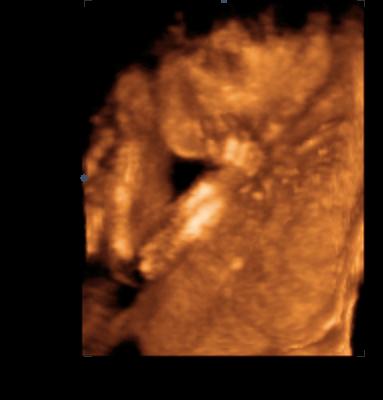

Timi: nagyon mocorgi Bíborka és a legédesebb, mikor nevetett. Tényleg csodás élmény lehet megélni, hogy már az anyaméhben látod a saját kis porontyodat... Annyira várom már, hogy mi is mehessünk.